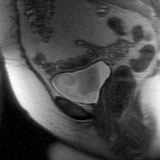

Sagittal T2-weighted image. The bladder has high signal intensity.